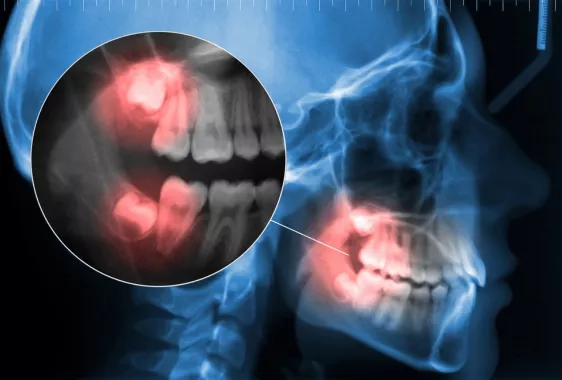

При подозрении на проблемное прорезывание, стоматолог дает рекомендации по дальнейшим действиям, направляет на дополнительные обследования. Расположение корней восьмерок отображается на рентгене и КТ.

На прицельном снимке видно точное положение, направление роста. Расположенные глубоко в кости восьмерки удобнее обследовать на КТ, так как она показывает не только костную массу, но и состояние мягких тканей. Томография дает трехмерное изображение, которое позволяет определить наклон, степень погружения зуба в кость, близость к нервам и пазухам.